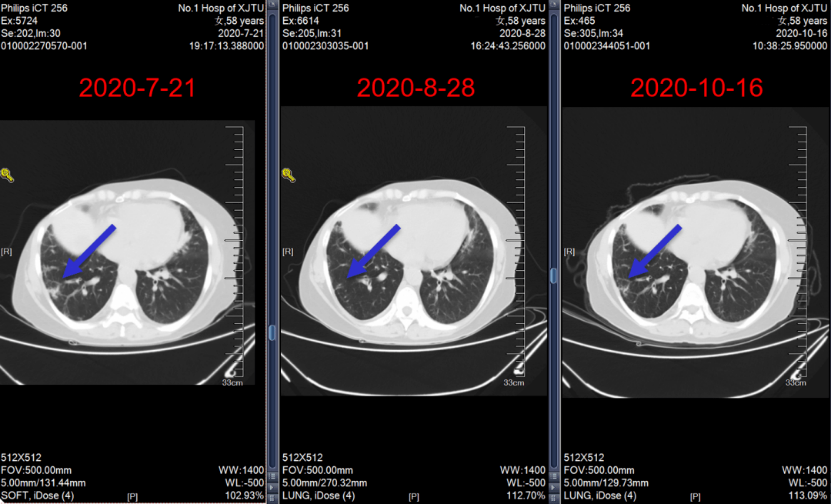

2020年7月23日~2020年10月16日,给予艾立布林(2 mg,d1,d8,q3w)×5周期抗乳腺癌治疗。

肺、肝脏转移病灶治疗2周期后部分缓解(PR),4周期后 SD。

图14:四线治疗期间随访肺部CT